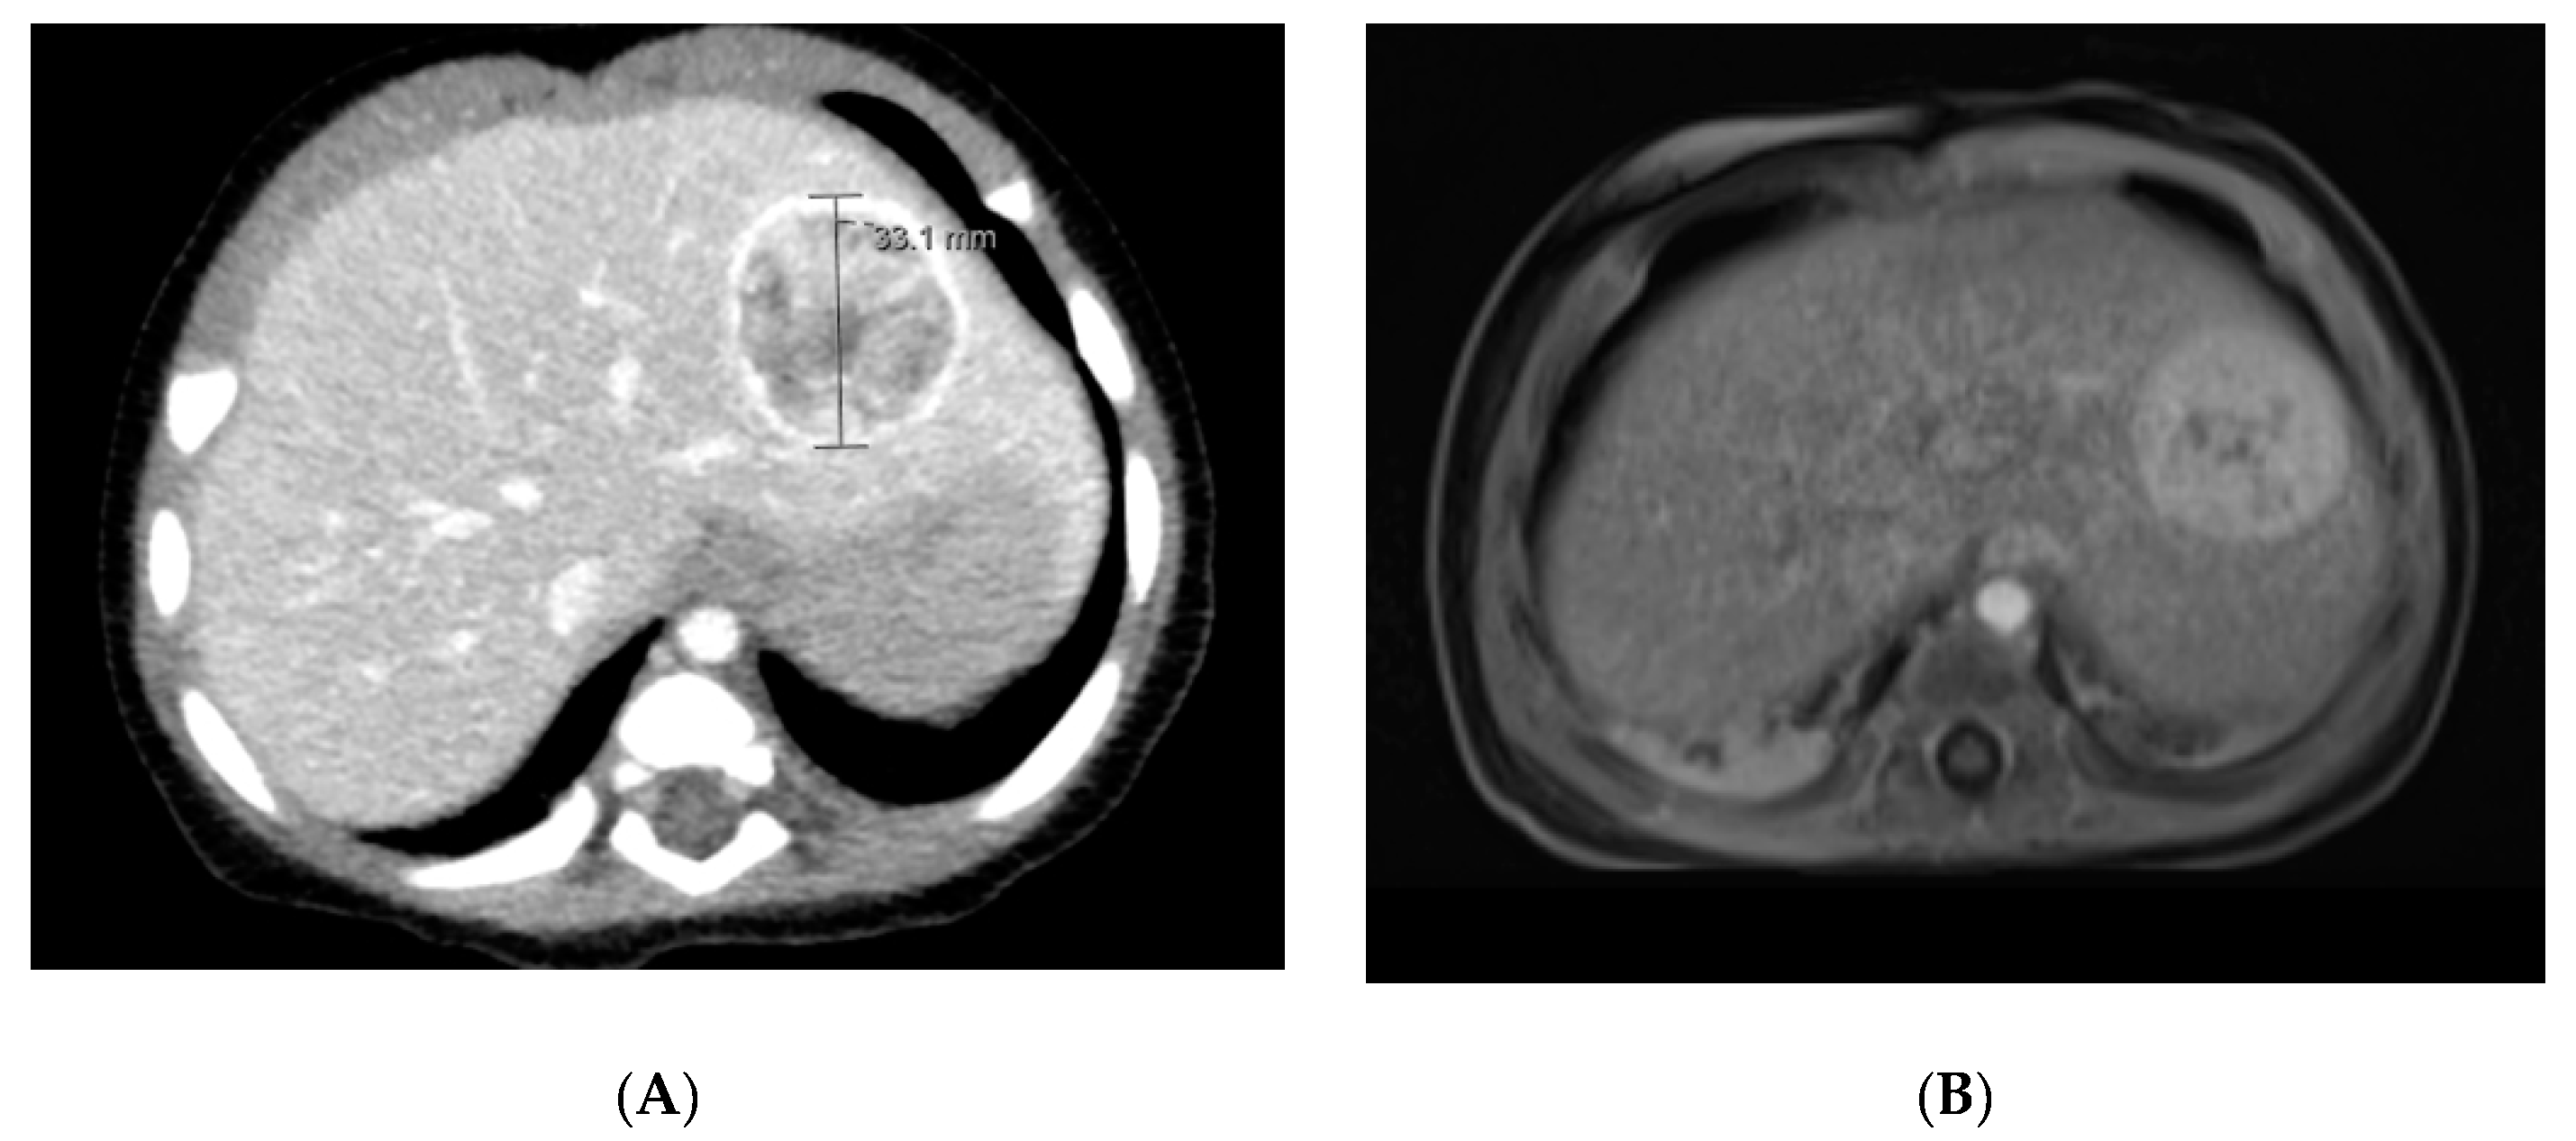

5.1.4. Diagnostic Imaging

5.2.4. Diagnostic Imaging